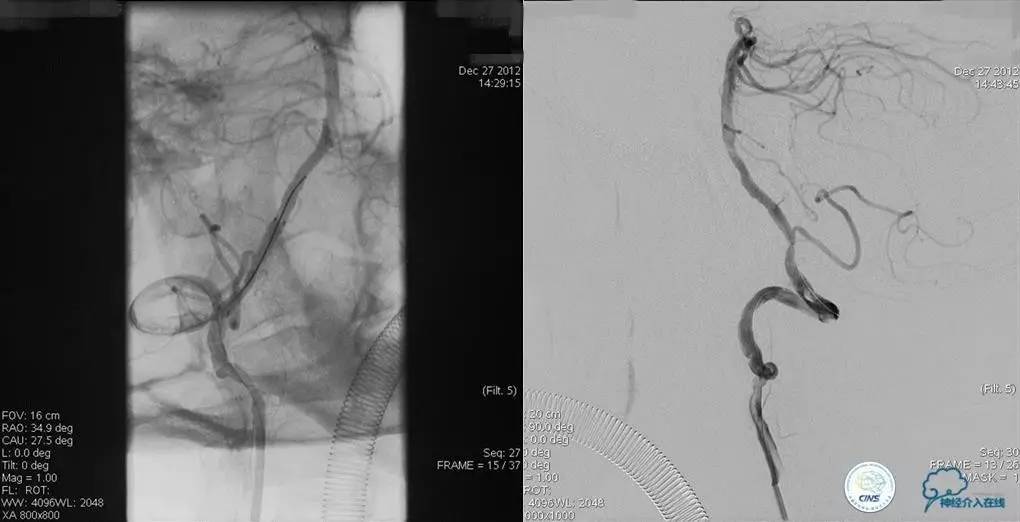

▼2013-12-27

术后仍残余部分狭窄,但头晕明显缓解。

术后3个月复查时予行支架内球囊扩张,狭窄改善。